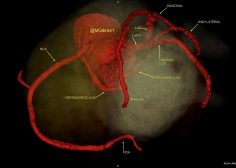

36Y male with chest pain, CT coronary shows a very rare anomaly. Twin LCX, (less than 10 cases in literature ).

The original LCX originates from LMCA , it supplies an early OM.

The 2nd anomalous LCX (arises from proximal RCA) with retro-aortic course till it reaches the left AV groove where it supplies a small OM.